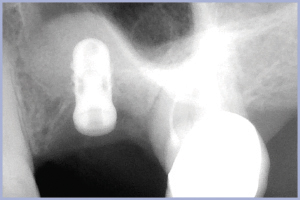

- Fig. 29 – Rx preoperatoria

1° Caso – Zona 2.6, osso crestale residuo 3,6 mm